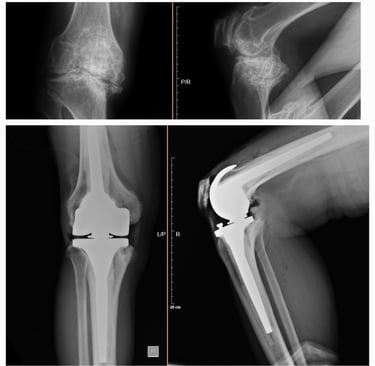

Tratamiento de lesiones severas de rodilla

Diagnóstico y tratamiento de daños importantes en ligamentos, meniscos, cartílago o hueso que afectan la estabilidad y movimiento de la rodilla. Dependiendo de la gravedad, puede requerir cirugía reconstructiva o reemplazo articular, siempre con el objetivo de recuperar la función, disminuir el dolor y permitir que el paciente retome sus actividades diarias o deportivas.

Cirugía en la que se reemplaza la articulación dañada por una prótesis nueva. Se realiza en casos de desgaste severo, artrosis o lesiones que provocan dolor intenso y limitan la movilidad. El objetivo es devolver la capacidad de caminar, realizar actividades cotidianas sin dolor y mejorar la calidad de vida.

Prótesis de cadera y rodilla